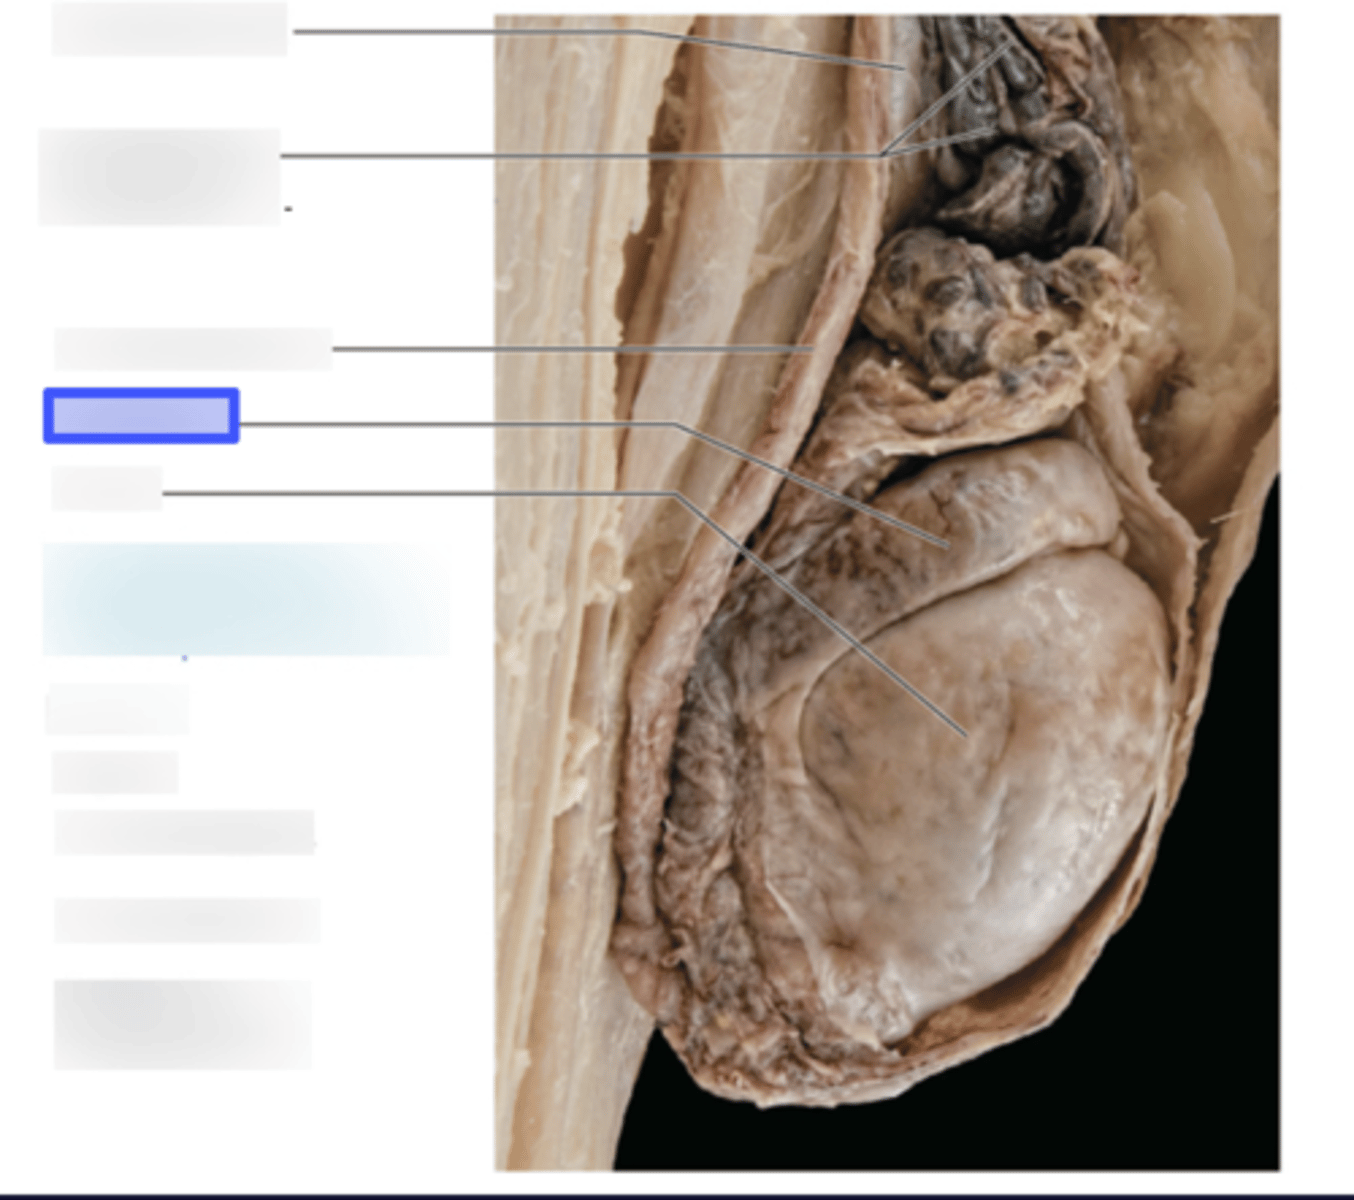

Renal Capsule

Renal Cortex

Renal Medulla

Papilla

Renal Column

Minor Calyx

Major Calyx

Renal Pelvis

Renal Hilum